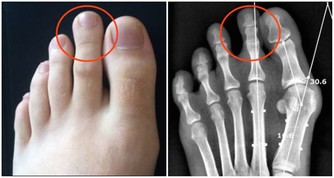

4、肺部有毒:合谷穴

肺部有毒的體現之一即是呈現便秘景象。